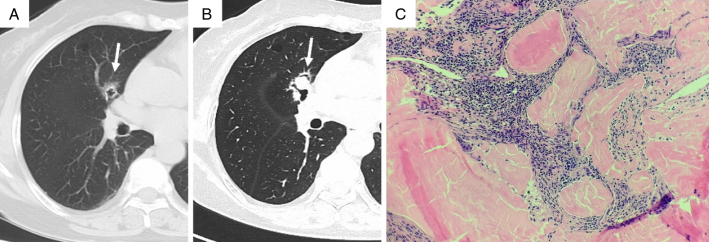

Results: Among the 13 patients, there were 3 males (23.08%) and 10 females (76.92%). Their ages ranged from 37 to 68 years, with a mean age of (57.85±8.40) years and a median age of 59 years. Three (23.08%) patients had cough and sputum, while the others (76.92%) had no clinical symptoms. Before surgery, 6 patients underwent chest CT scans, and NPA changes in size, shape, and density were observed. Six cases (46.15%) were located in the left lung (4 in the upper lobe and 2 in the lower lobe), and 7 cases (53.85%) in the right lung (3 in the upper lobe, 2 in the middle lobe, and 2 in the lower lobe). Seven cases (53.85%) of NPA were round or oval, while 6 cases (46.15%) were irregularly shaped. Out of the NPA cases, 11 (84.62%) were solid nodules with well-defined boundaries, including 2 cases of solid nodules with surrounding calcification. In addition, 2 cases presented as solid nodules with cavities. Ten cases (76.92%) had multiple cystic lesions in the bilateral lungs, in which 7 cases had more than 10 cysts with obvious cyst walls, and 1 case showed a solid nodule on the cyst wall. During the postoperative follow-up, 1 patient experienced an increase in the size of the original nodule and the appearance of new solid nodules. Subsequent surgery revealed mucosal-associated lymphoid tissue lymphoma (MALT). The remaining patients were followed up regularly, and their conditions remained stable.

Conclusions: NPA is more common in middle-aged and elderly people and is more likely to occur in women. Most cases are asymptomatic, and bilateral lungs can be involved. For nodules with multiple pulmonary cysts found by chest CT, the possibility of NPA should be considered, and further histopathologic examination is needed to confirm the diagnosis. Most patients with NPA have a good long-term prognosis after surgical resection, but some patients require further investigation and close follow-up due to underlying causes.